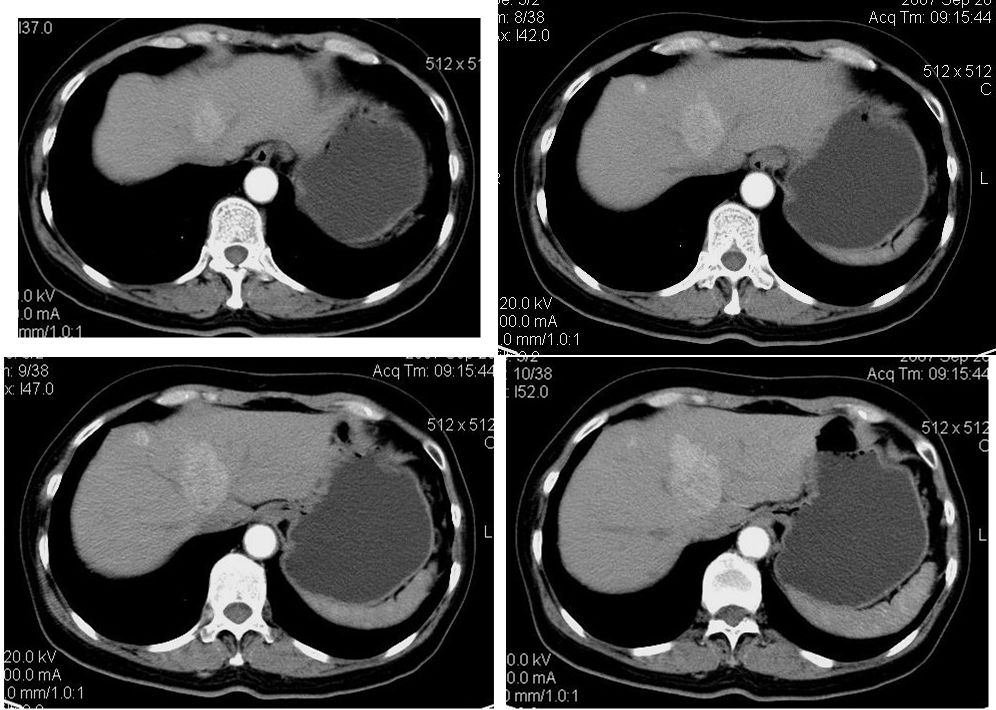

患者,女,65岁,住院准备甲状腺腺瘤用术,术前常规发现肝脏占位,ct增强扫描。

平扫

动脉期

门脉期

延迟扫描

肝左叶内侧段低密度灶,增强明显快进快出表现,考虑:肝癌。

该患者去年9月份在我院ct检查,今年随访,患者家属介绍说上海中山医院做了一个什么检查考虑良性占位,后手术病理是血管平滑肌脂肪瘤。

学习了,这可能是脂肪含量少的血管平滑肌脂肪瘤,因血管丰富所以动脉期密度升高明显,但该患无肝硬化表现,所以,诊断肝癌,依据不足.谢谢上传.对今后工作是一个提醒.